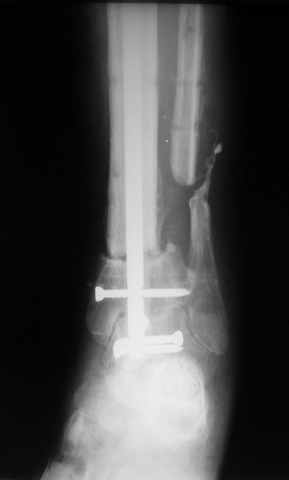

Ситуация пока на следующем этапе:

Больному выполнена резекция малоберцовой кости, ВХО раны, сближение отломков. Резекция м\б через отдельный разрез. После ВХО компрессия в аппарате, края раны сближены наводящими швами (без натяжения).

В случае гладкого заживления раны, при условии положительного решения вопроса с металлом, планируем перемонтаж аппарата Илизарова, дополнительную резекцию дистального отломка, выведение полокости голеностопного сустава в правильное положение (см. боковую Р-грамму), одномоментно остеотомия большеберцовой кости. После восстановления длинны голени, по всей видимости, артродез голеностопного сустава.

Рентгенограммы прилагаются. Фото местного статуса выложу в ближайшее время.

Мы обычно не фиксируем малоберцовую кость. Просто стараемся сопоставить ее концы за счет хорошей репозиции. В представленном случае имеется некоторое смещение дистальных фрагментов кнаружи, и, как мне кажется, ротация их вместе со стопой кнутри (ротация хорошо заметна на прямом снимке по форме таранной кости и на боковом по соотношению отломков малоберцовой). Если это действительно так, то это несложно сейчас постепенно устранить в аппарате. И тогда концы малоберцовой кости будут находиться поближе друг к другу.

И еще. Если доктора решат делать артродез, то при артродезировании штифтом через пятку особых проблем с нестабильностью дистального отломка большеберцовой кости не возникает. Даже при том обстоятельстве, что уже где-то через месяц после операции пациент ходит почти с полной нагрузкой на ногу. Такого рода проблемы чаще бывают при лечении спице-стержневым аппаратом. Переломы в нижней трети голени в аппаратах частенько срастаются с большой неохотой. Правда в этой ситуации наша совесть абсолютно чиста - мы не повреждаем таранно-пяточный сустав. Пока лежит аппарат этот сустав приходит в полную негодность самостоятельно, всего лишь за 4-6 месяцев.